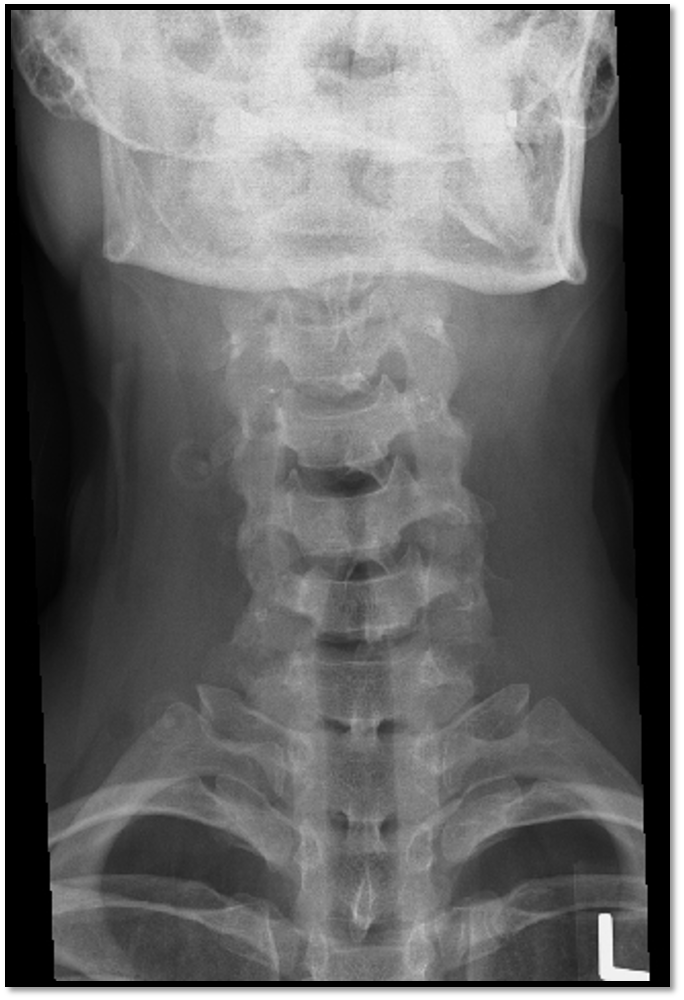

AP Axial Cspine criteria

A

• occipital bone and mandible lined up (extension)

• spinous process midline (rotation)

• open vertebral discs (angle)

• all of C3 is visible

• need to lift the chin more

• all of C3 is demonstrated